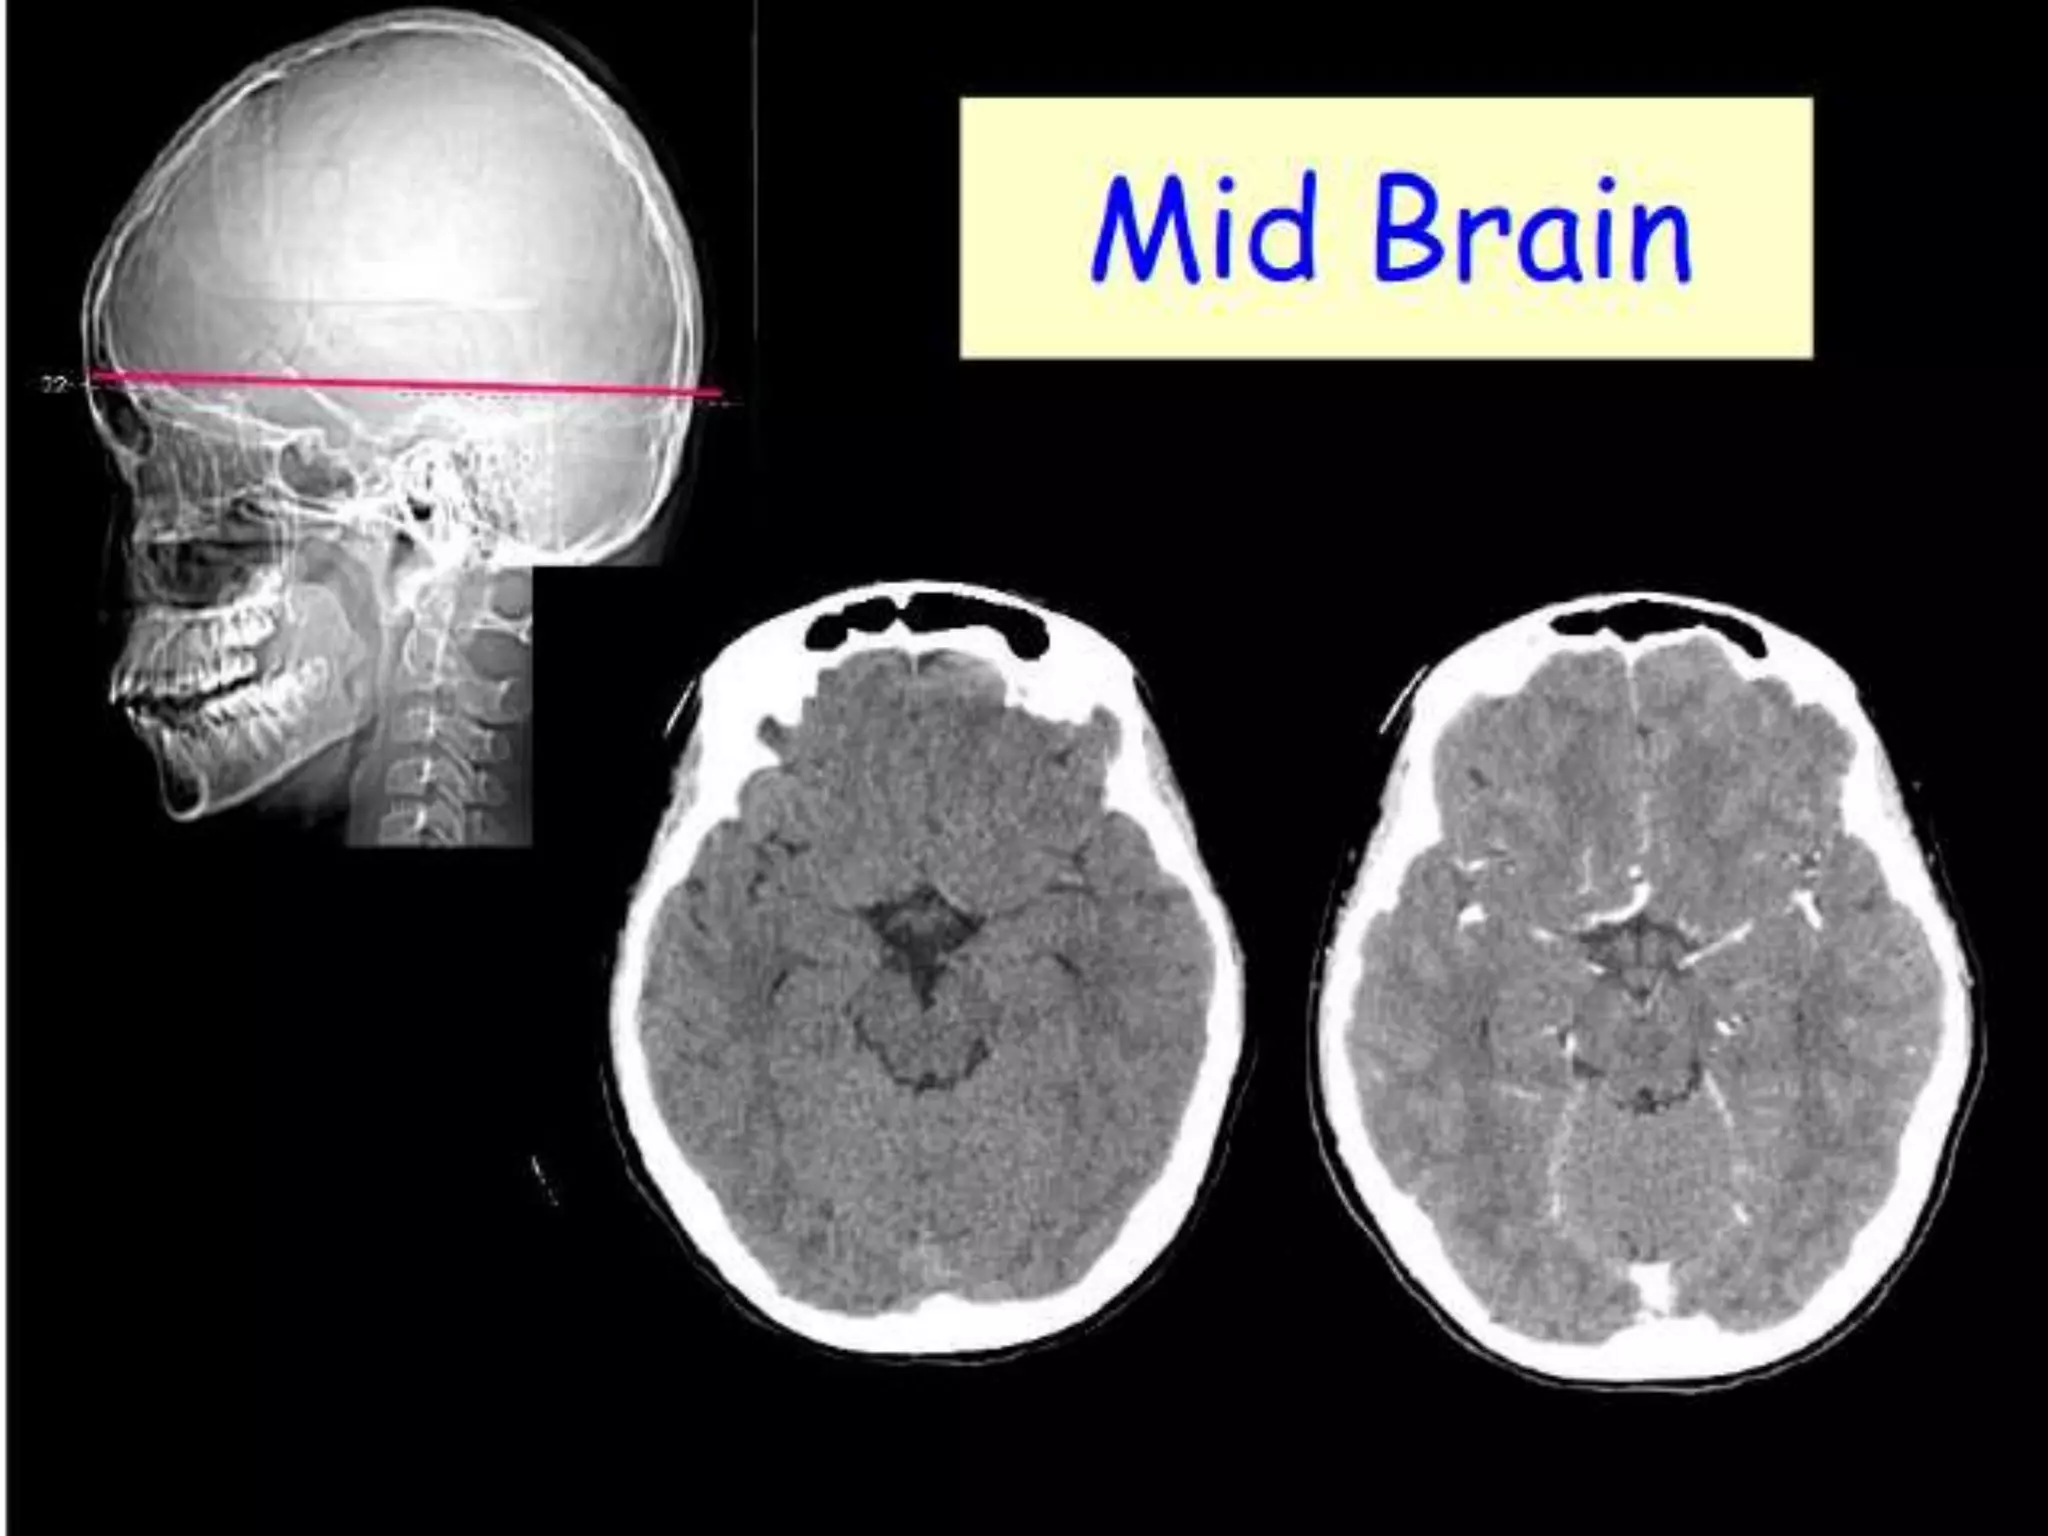

On CT and MR scans, the brain has been briefly viewed in

infratentorial and supratentorial sections, as described below.

CT scans are performed with a 15- to 20-degree angulation to

the canthomeatal line at 8-mm increments. MRI scans are

generally obtained parallel to the AC-PC line in the axial plane

with 6-mm slice thickness. Using the sagittal view, the coronal

sections are acquired parallel to the brain stem, and the

sagittal sections are obtained perpendicular to the axial

section.

Sectional Anatomy: NormalAxial CT and MRI Anatomy. On CT and MR scans, the brain has been briefly viewed in infratentorial and supratentorial sections, as described below. CT scans are performed with a 15- to 20-degree angulation to the canthomeatal line at 8-mm increments. MRI scans are generally obtained parallel to the AC-PC line in the axial plane with 6-mm slice thickness. Using the sagittal view, the coronal sections are acquired parallel to the brain stem, and the sagittal sections are obtained perpendicular to the axial section. On MRI studies, cranial nerves IX and X can be demonstrated at this level because they emerge from the postolivary sulcus. The posterior aspect of the cerebellar hemispheres is outlined by the inferior portion of the cisterna magna.